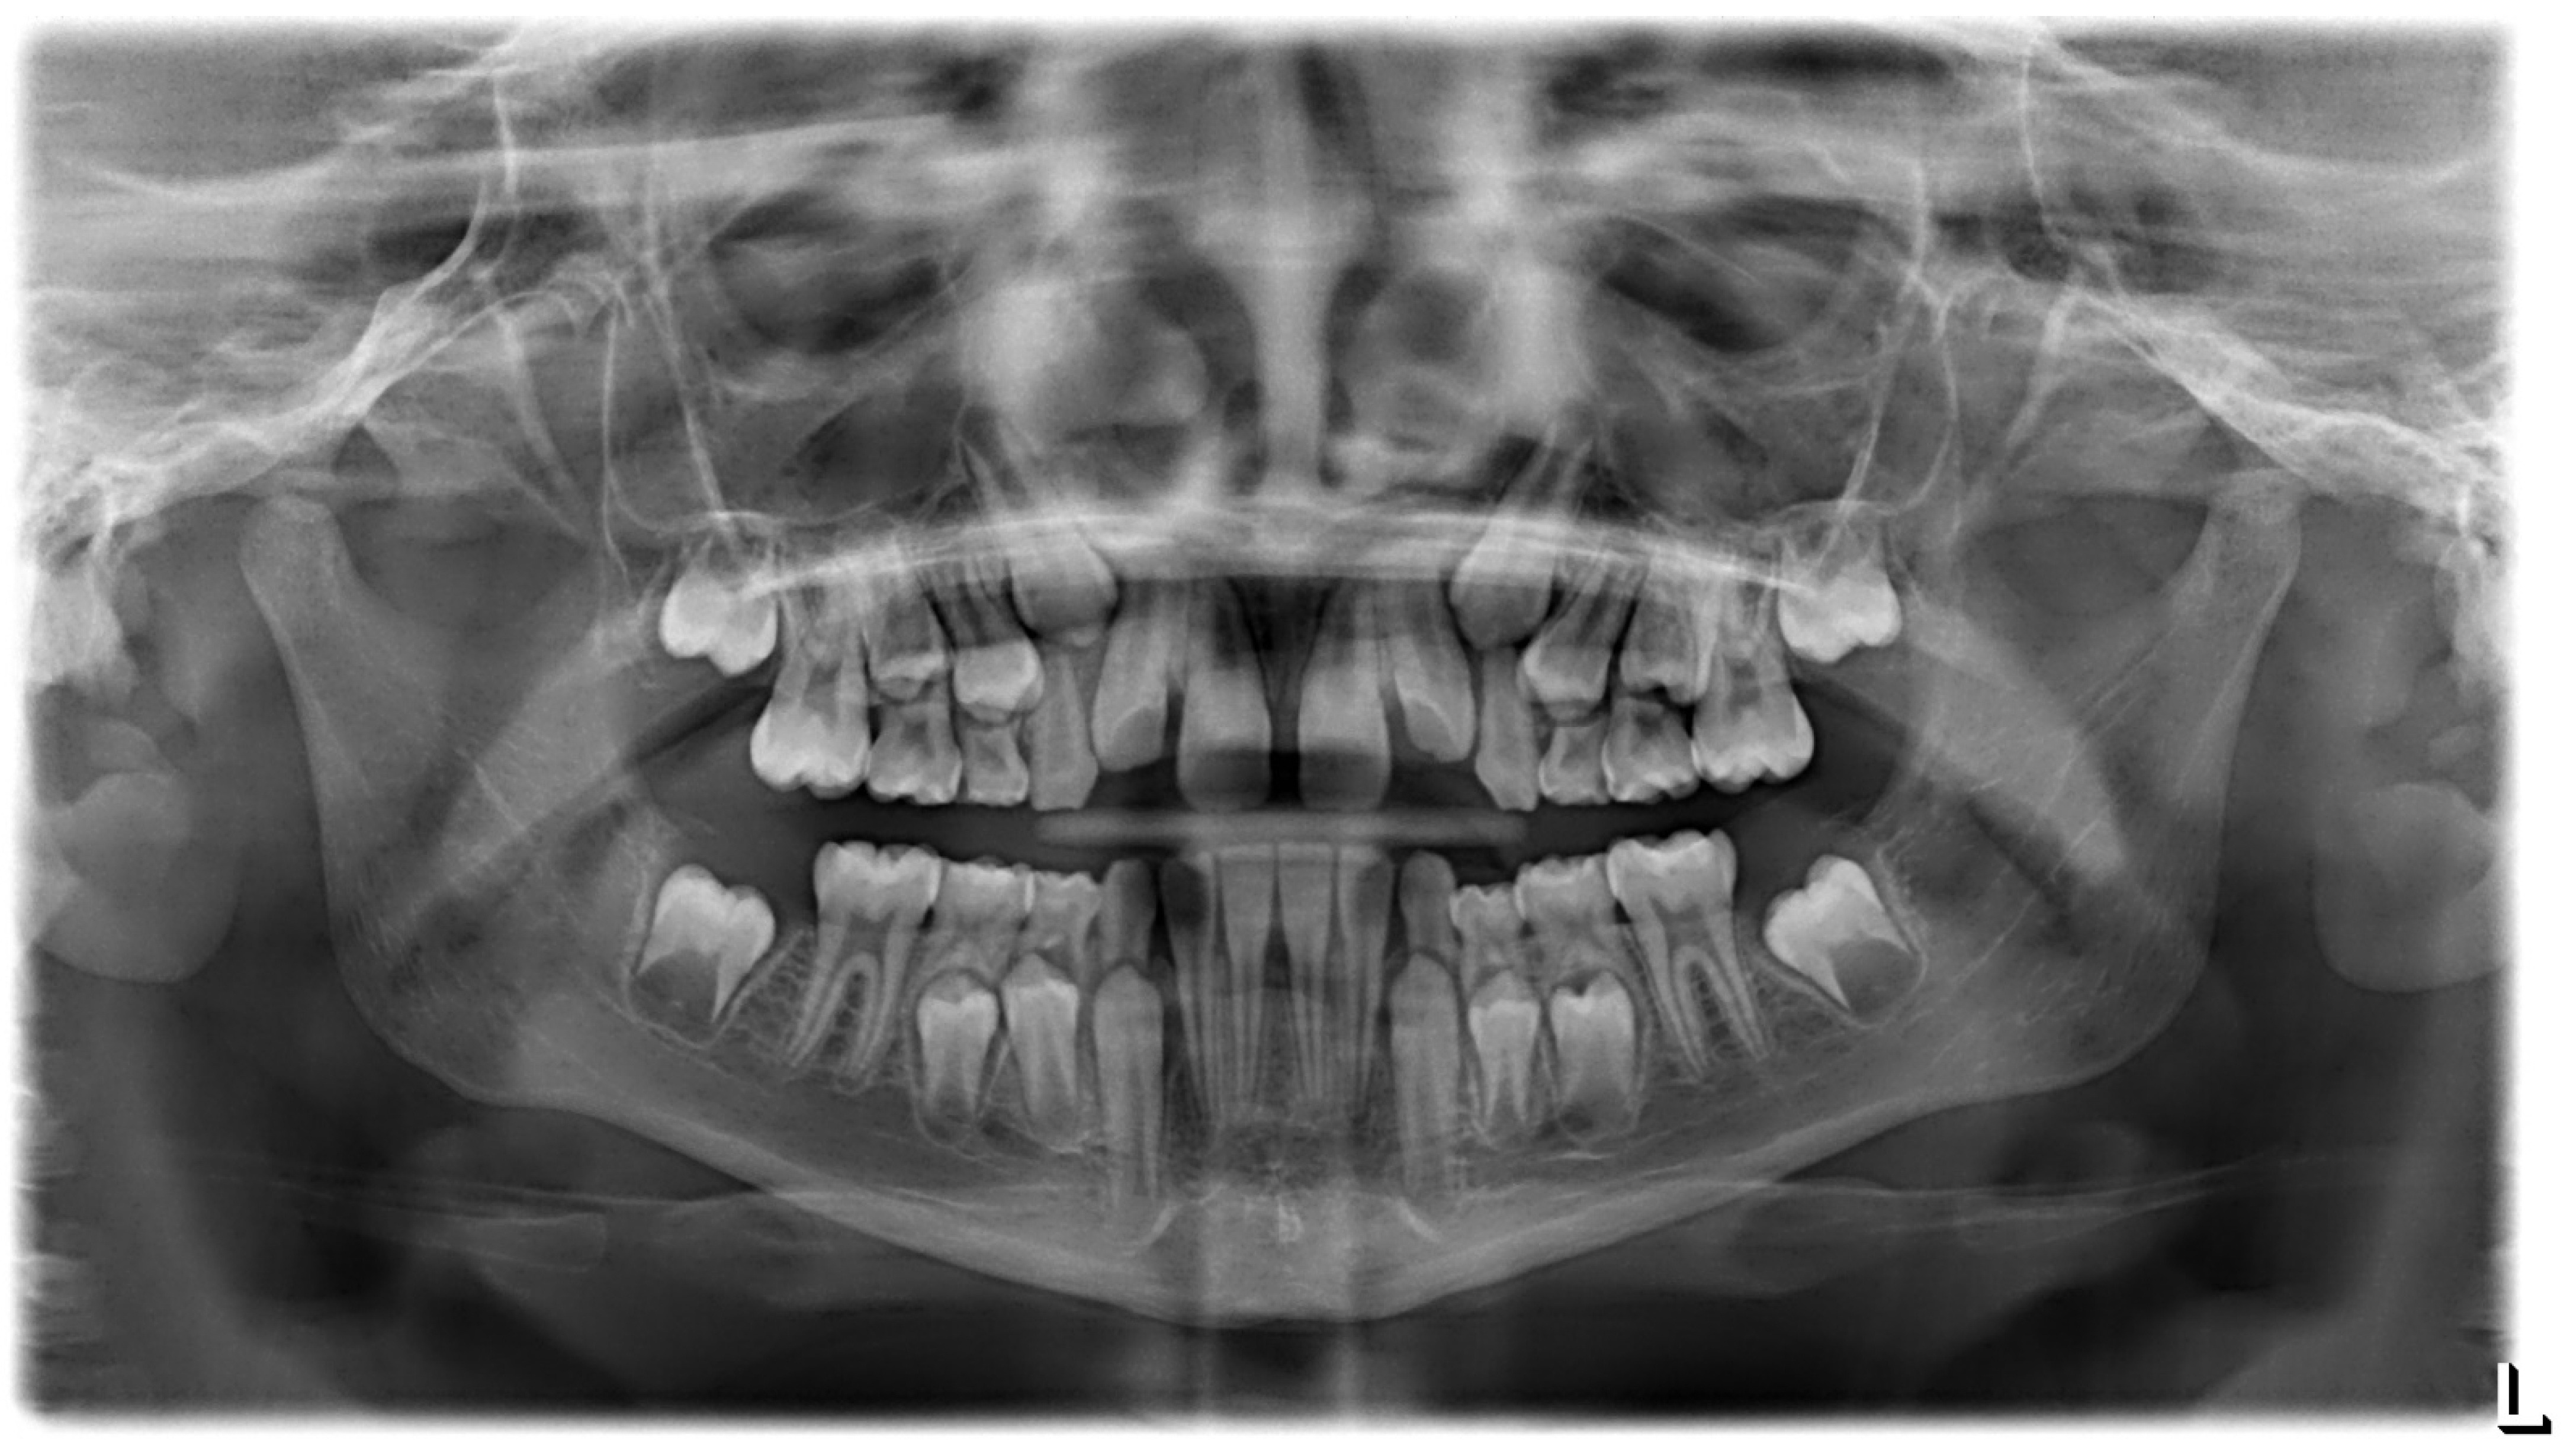

3.1. Clinical Case #1

3.2. Clinical Case #2

3.3. Clinical Case #3

3.4. Clinical Case #4